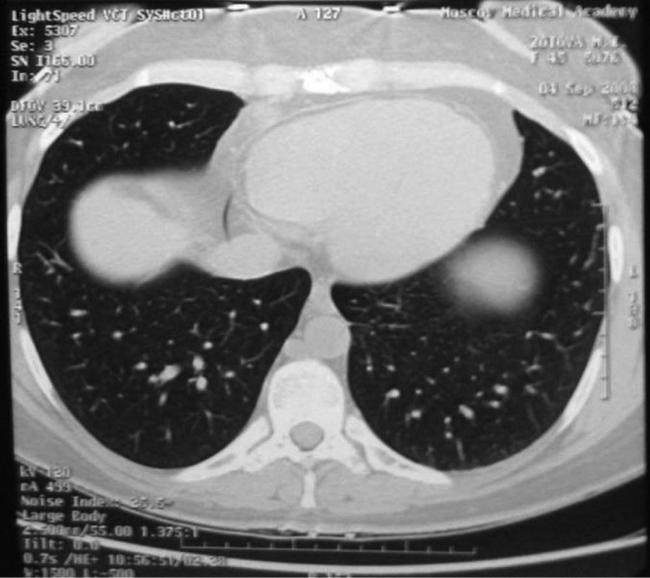

Почему возникают и чем опасны очаги в легких

Существует определенная разница между международно установленным понятием очаговых образований, и тем, что принято в отечественной медицине. За рубежом к ним относят уплотнения в легких размером около 3 см. Отечественная медицина ставит ограничения до 1 см, а другие образования относит к инфильтратам.

Компьютерная томография способна с большей вероятностью установить размер, форму уплотнения легочной ткани. Это исследование тоже обладает процентом погрешности.

Очаговые образования в органах дыхания представлены в качестве дегенеративных изменений в тканях легких или скапливании жидкости в виде мокроты или крови. Многие специалисты считают одной из важных задач их установление.

До 70% одиночных очагов в легких относятся к злокачественным новообразованиям. С помощью КТ (компьютерной томографии), и базируясь на специфических симптомах, специалист может предположить о возникновении таких опасных патологий, как туберкулез или рак легких.

Однако для подтверждения диагноза требуется сдать необходимые анализы. Аппаратного обследования для получения медицинского заключения в некоторых случаях недостаточно. У современной медицины не существует единого алгоритма для проведения исследований при всех возможных ситуациях. Специалист рассматривает каждый случай отдельно.

Провести аппаратным методом четкую диагностику заболевания не позволяет несовершенство оборудования. При прохождении рентгенографии легких трудно обнаружить очаговые изменения, размер которых не достигает 1 см. Интерпозиция анатомических структур делает невидимыми и более крупные образования.

Специалист предлагает больным пройти обследование с помощью компьютерной томографии. Она позволяет рассмотреть ткани под любым углом.